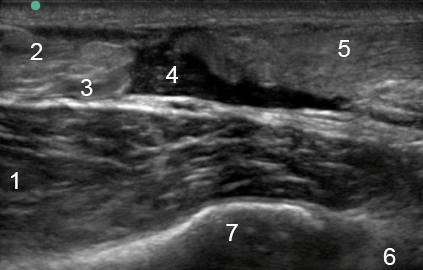

Foot & Ankle Achilles Tendon Tear Longitudinal Image

1. Flexor Hallucis Longus (FHL)

2. Achilles

3. Soleus

4. Tear Gap

5. Achilles

6. Talus

7. Tibia